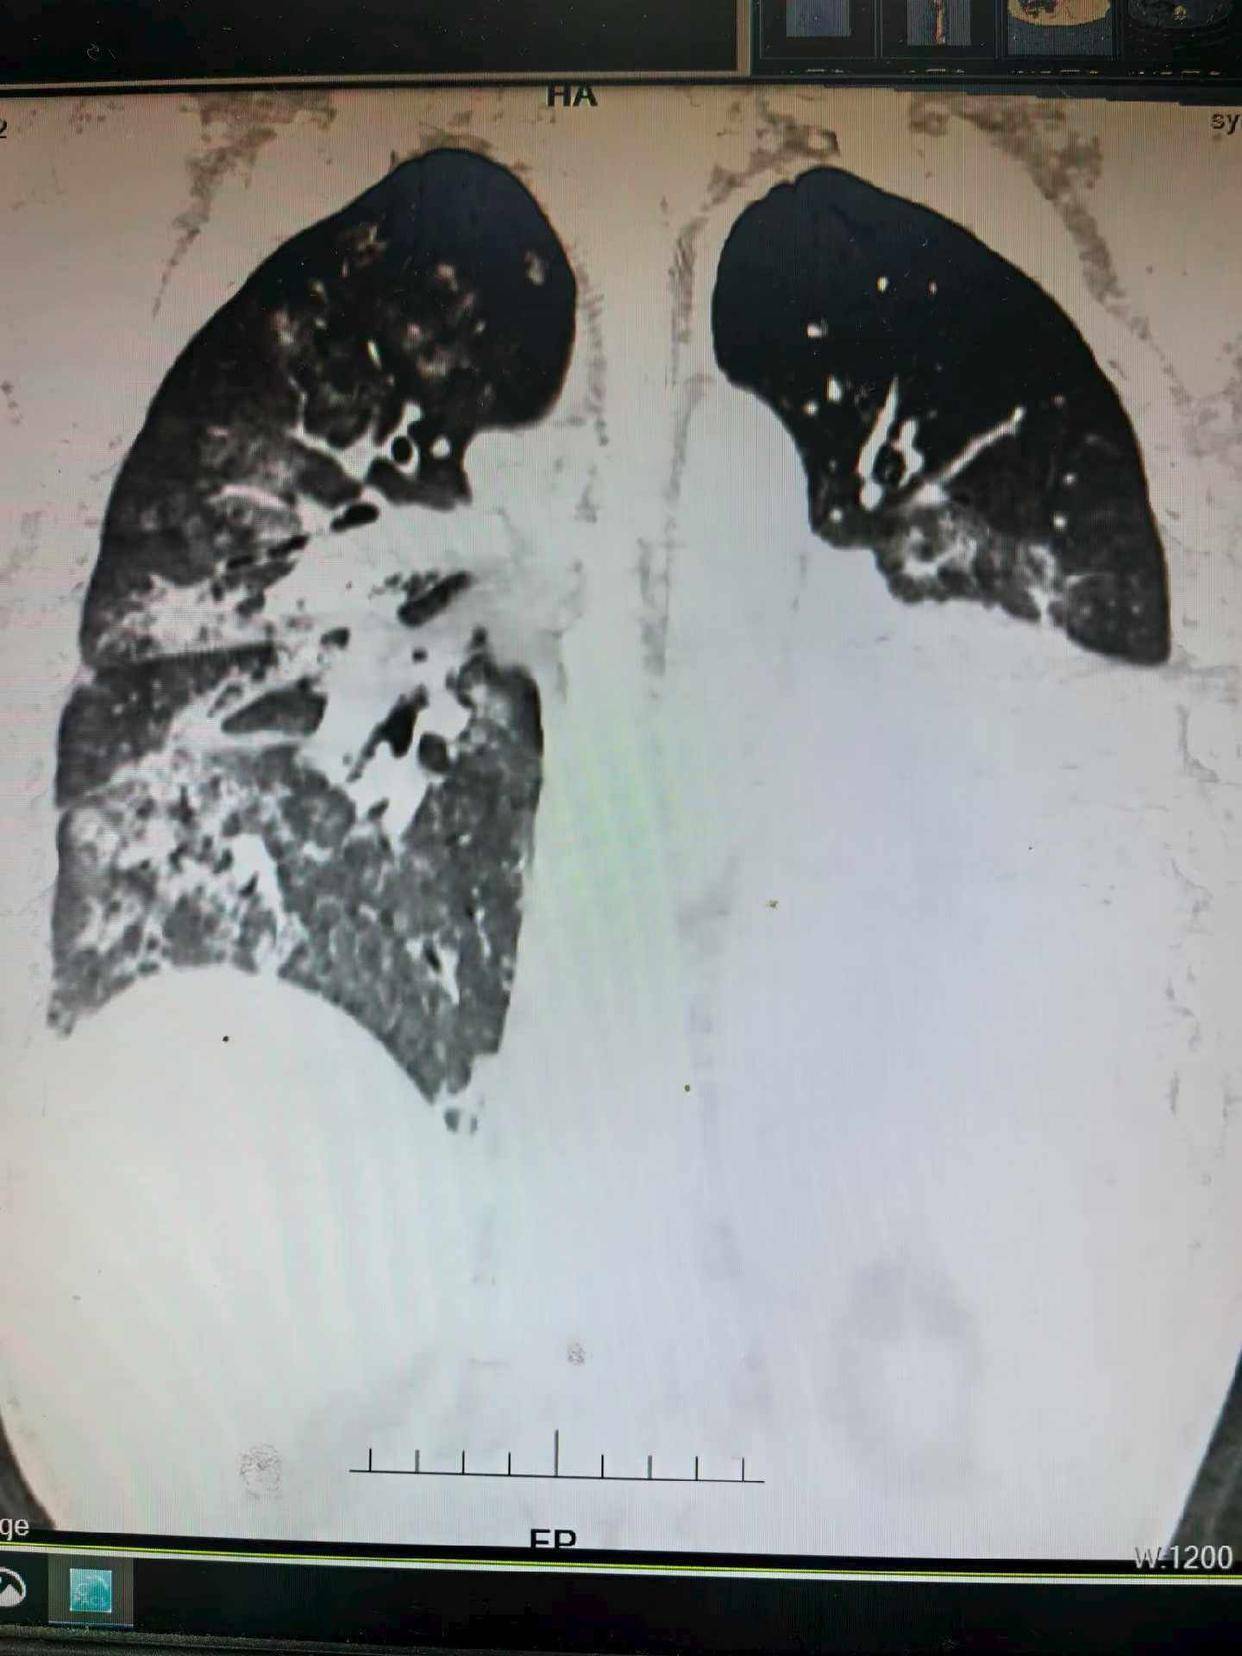

在后续CT检查中,医生发现其左肺形成了肺脓肿,并且发生了支气管胸膜瘘。“这意味着感染灶持续存在,像一个定时炸弹。”周利平教授说。为了彻底清除病灶,经过多学科团队的慎重评估,最终为他实施了左下肺叶切除术。当感染的核心被切除,这场持久战终于迎来了转折点。术后约一周,患者即出院返渝。据随访,患者复查肺部CT显示恢复良好。

“面对如此复杂的危重症,单靠一个科室不可能完成,而湘雅医院综合救治能力是患者安全的最大托举。”湘雅医院急诊科李湘民主任介绍,76天里多学科团队如同精密运作的救援网络。急诊、血液、重症、胸外、呼吸、介入、输血等科室深度协作,进行了4次大型多学科会诊。支气管镜做了12次,胃镜6次,CT引导下的肺脓肿穿刺引流2次,前期还进行了2周持续血液净化治疗,“每一天都是在和死神赛跑”。